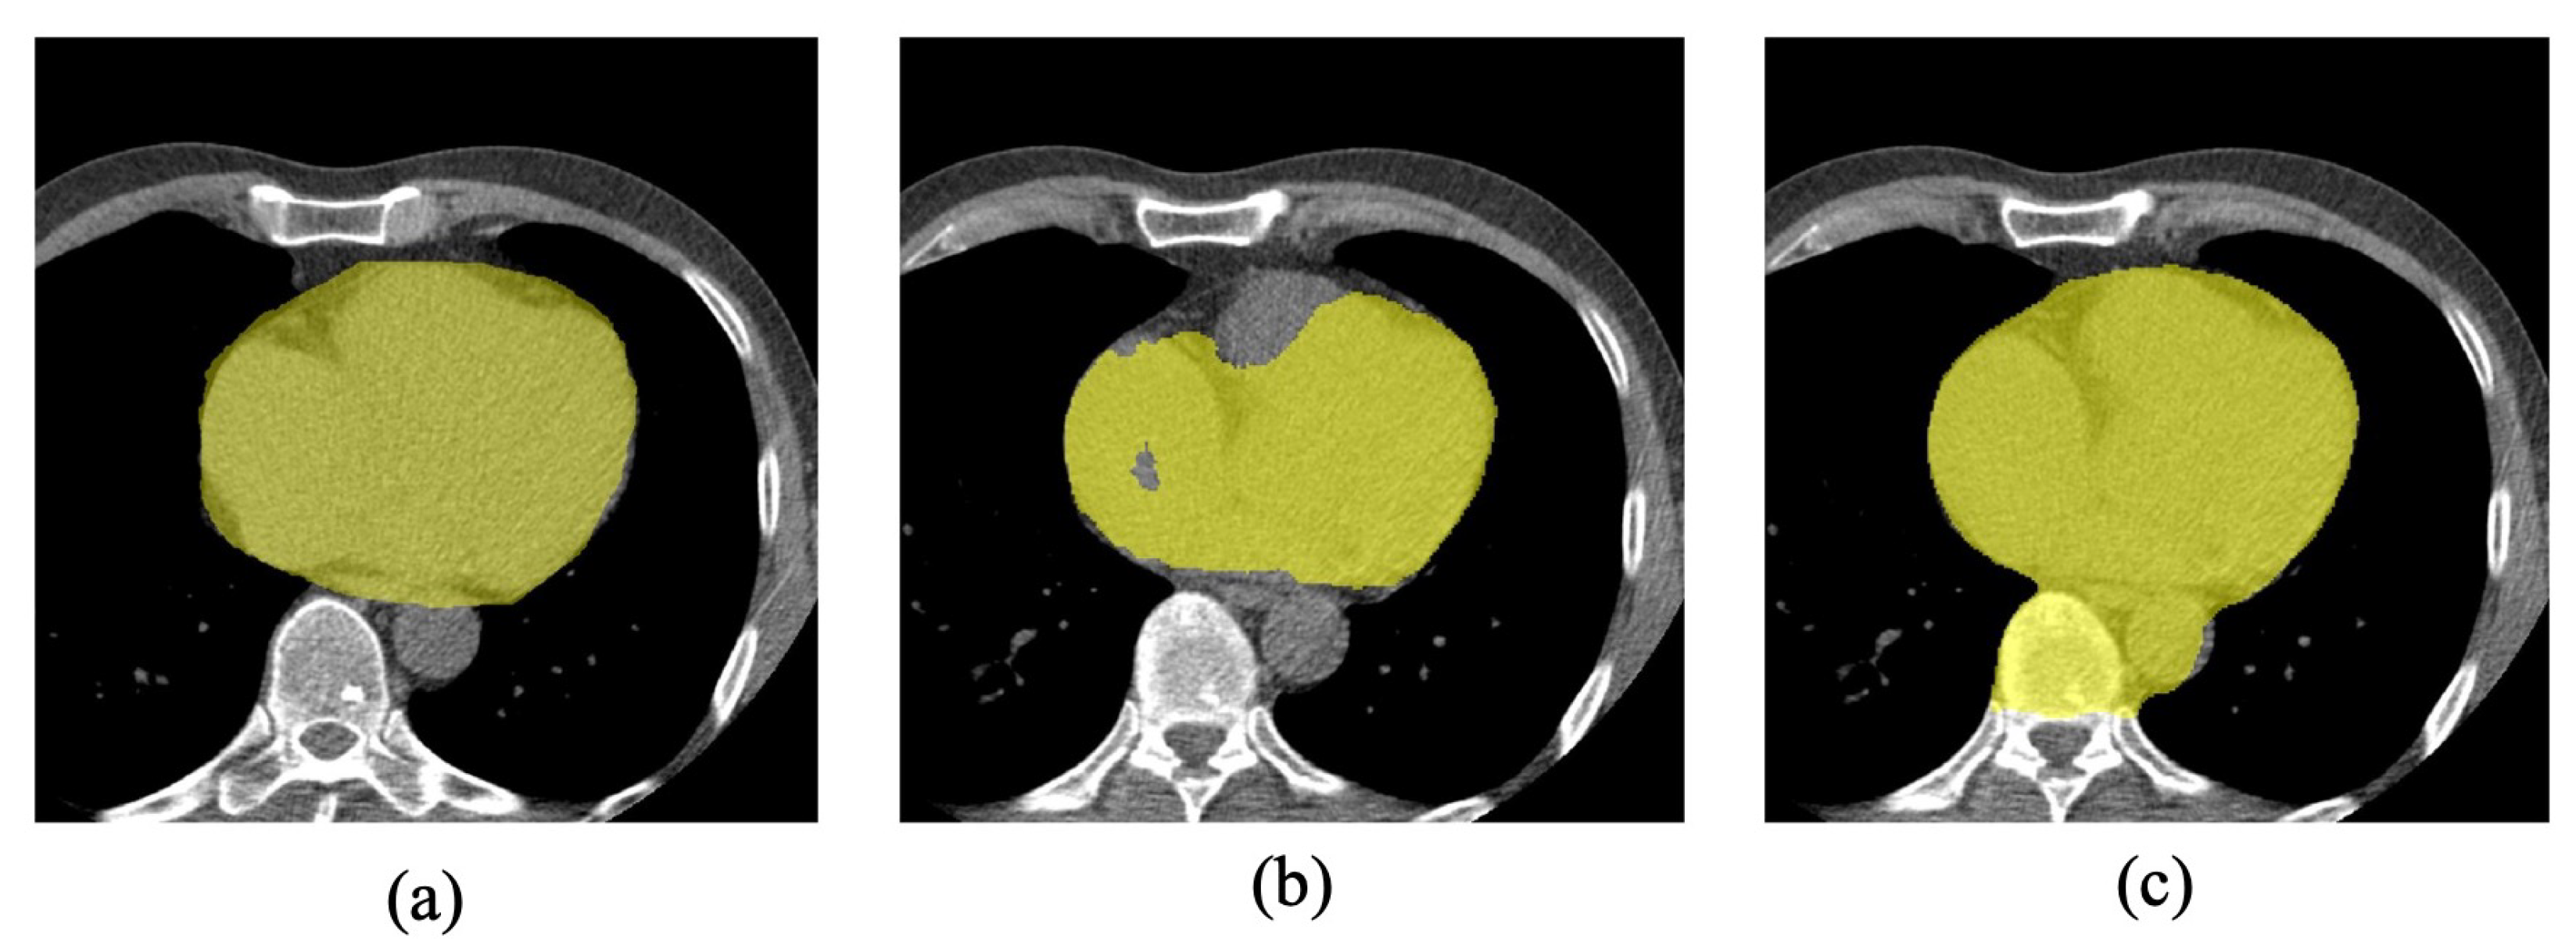

2.1. Data Set-Up